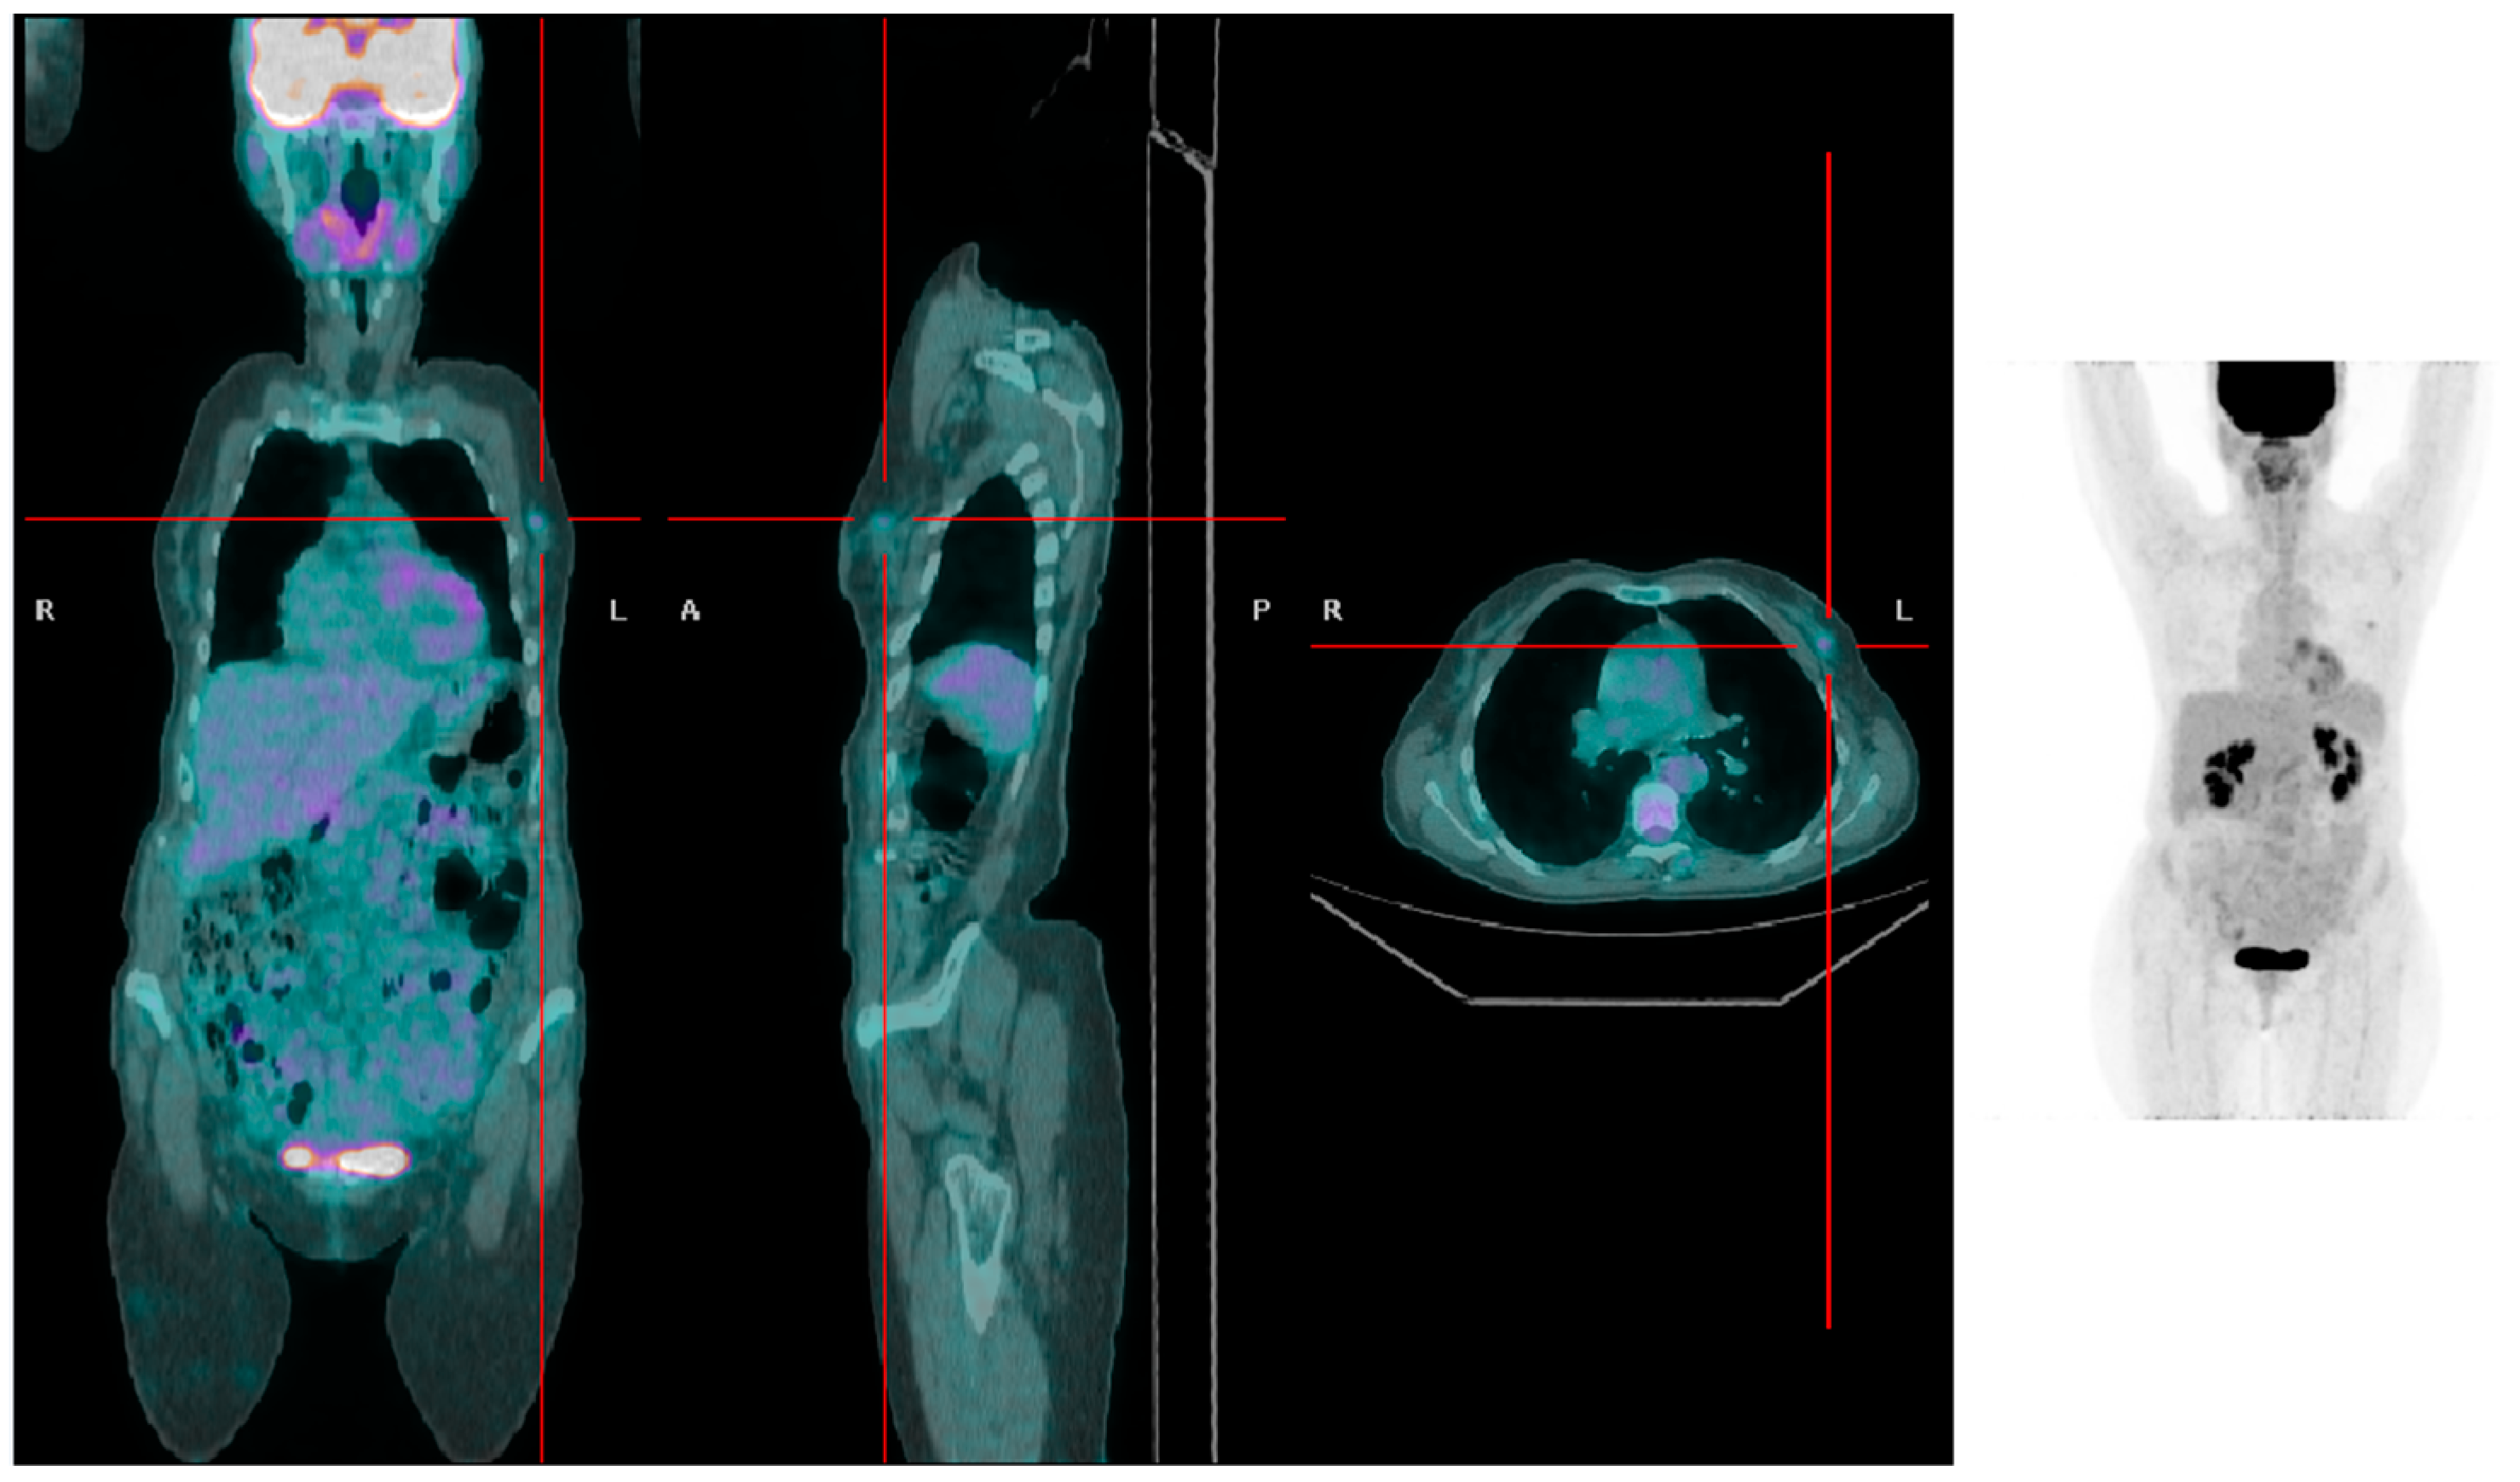

There were 48 recurrences at the follow-up (35 in the overweight group and 13 in patients with normal weight). The chi-square test demonstrated a higher frequency of recurrences in overweight women compared to women with a BMI < 25 kg/m2 (35 vs. 13; p = 0.025). The local and regional recurrence rates were 17.85% and 25% in the overweight patient group and 3% and 12% in the normal weight patient group, respectively. A significantly higher frequency of T_rec (15 vs. 2; p = 0.018) and a higher T_rec SUVmax (4.74 ± 2.90 vs. 1.85 ± 0.63, respectively; p = 0.09; Figure 1 and Figure 2) were found in overweight women compared to women with a BMI < 25 kg/m2. No statistically significant difference between the two groups was found for the frequency of N_rec and M_rec. SUVmax of N_rec was significantly higher in overweight patients compared to patients with BMI < 25 kg/m2 (6.57 ± 4.08 vs. 3.14 ± 1.62, respectively; p = 0.004).

Figure 1.

A patient with low BMI presenting with a left-sided breast tumor with mild [18F]FDG uptake (SUVmax 1.5).